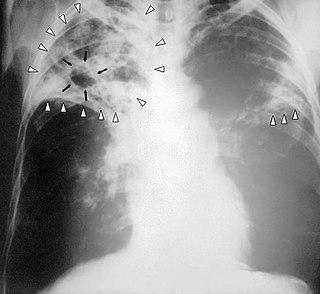

Туберкулёз — широко распространённое в мире инфекционное заболевание человека и животных, вызываемое различными видами микобактерий из группы Mycobacterium tuberculosis complex, или иначе палочками Коха. Туберкулёз обычно поражает лёгкие, реже затрагивая другие органы и системы. Mycobacterium tuberculosis передаётся воздушно-капельным путём при разговоре, кашле и чихании больного. Чаще всего после инфицирования микобактериями заболевание протекает в бессимптомной, скрытой форме (тубинфицированность), но примерно один из десяти случаев скрытой инфекции, в конце концов, переходит в активную форму. Для человека заболевание является социально зависимым.